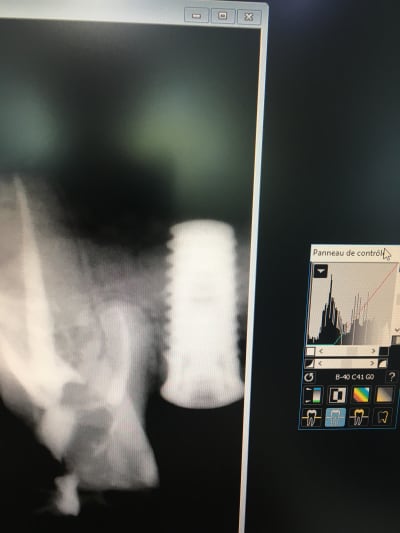

Bonjour chers confrères et consoeurs, j'ai besoin de votre aide pour identifier cet implant ( dentiste poseur en retraite, plus de dossier).

"la mesure" sur la rétro donne un diametre de 3.8 ou 4 et 10 de long .

j'en peux plus des captures d'écran merdiques au smartphone qui bouffent 50% des détails nécessaires à une bonne identification!!!

mais là pour l'instant je fais choux blanc (enfin disons plutôt que j'ai plusieurs pistes)...çà serait pas mal si tu pouvais faire une radio bien centrée sur l'implant que je puisse avoir un max de détails....

Qq'un m'a parlé de IDI mais l'extrémité apicale de l'implant parait plus plâte dans mon cas.

le truc qui colle le mieux, c'est un osstem SS3...mais j'ai des doutes....